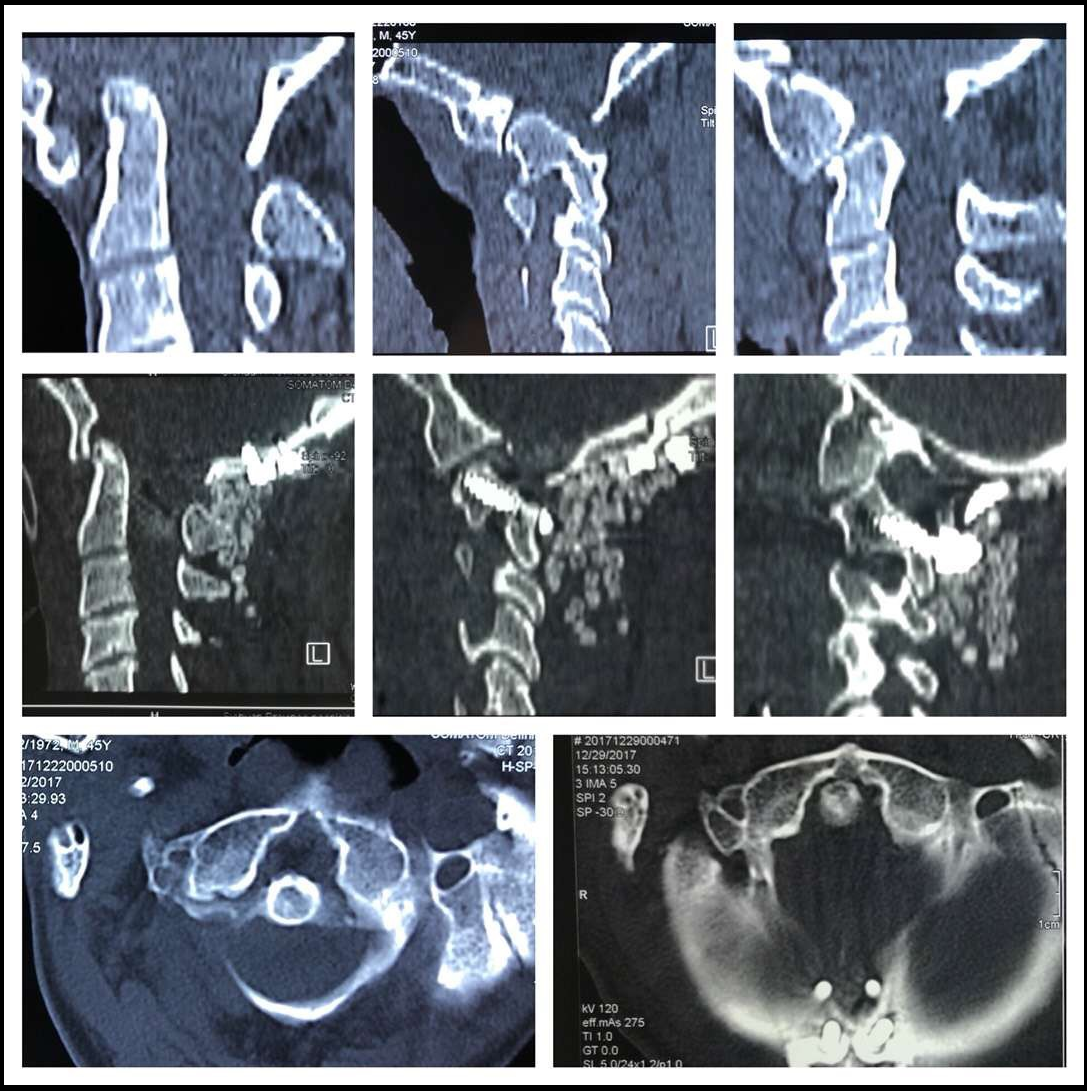

难复性环枢脱位